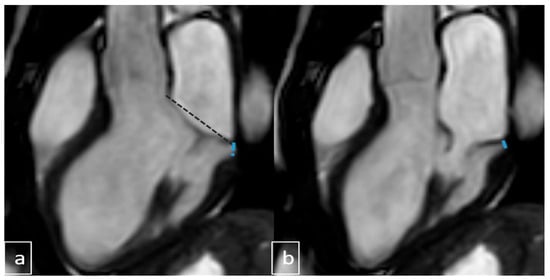

2.4. Image Analysis

3.6. Cardiac MRI Findings in MAD